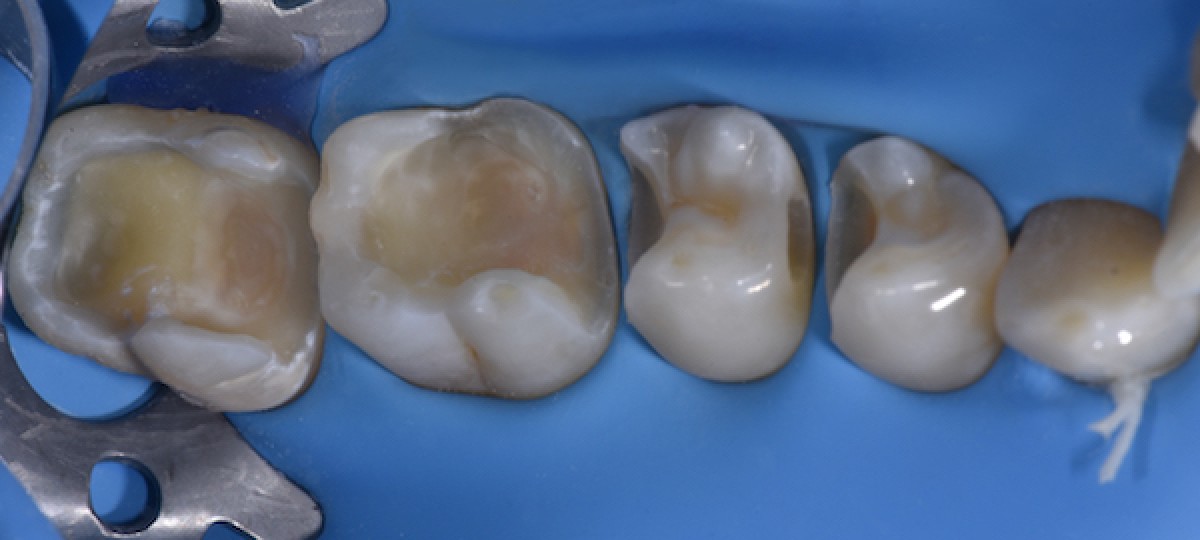

After initial cavity cleaning, it was possible to observe a crack of the mesio-lingual cusp of 4.6. (Fig.3)

The cracked cusp thickness was measured with a caliber. A thickness under 1.5mm was found in the upper third of the cusp, which was not supported by sound dentin (Fig.4)